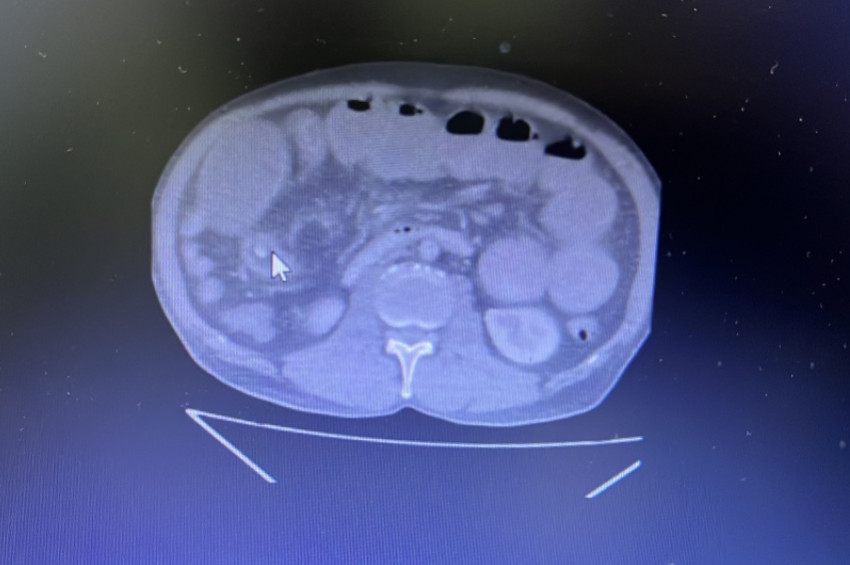

Uzun süredir mide yanması şikayeti bulunan Gül, arkadaşının "Hastalığına iyi gelir." tavsiyesiyle 4 zeytin yuttu. Mide yanması karın ağrısı, bulantı ve kusmaya dönüşünce özel bir hastaneye kaldırılan Gül'ün ince bağırsağında tümöre benzer bir cisim tespit edildi. Acil ameliyata alınan Gül'ün ince bağırsağında tümör zannedilen kitlenin zeytin olduğu anlaşıldı.

İlk etapta kitlenin zeytin olabileceğinin akıllarına gelmediğini belirten Yılmaz, "Açıkçası ben safra taşı olabilir diye düşünmüştüm, ameliyat işlem sırasında tıkanıklık olan yeri açtığımızda içinden zeytin tanesi çıktığını gördük." dedi.

Vatandaşlara meyve ve sebzelerin çekirdeklerini yememeleri tavsiyesinde bulduklarını vurgulayan Yılmaz, "Mide rahatsızlığı bulunanların doktora gidip muayene olduktan sonra endoskopi yapılıp ona göre ilaç kullanmalarını tavsiye ediyoruz. Hastamız ameliyattan önce 2 haftadır büyük abdestini yapamıyordu. Şu an hastamızın gayet iyi durumda." diye konuştu.